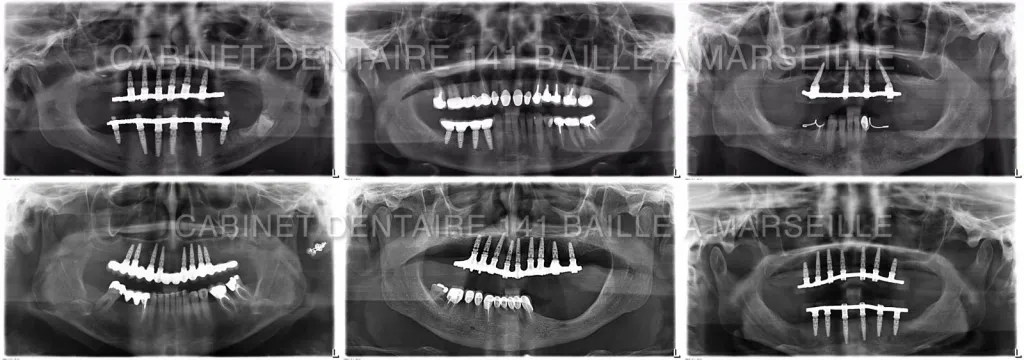

Effectivement aujourd'hui la technique de mise en charge immédiate des implants appelée MCI , permet au cours d'une seule intervention de procéder au remplacement de toutes les dents par des implants.

Le spécialiste en implantologie dentaire effectue l'extraction des dents malades s'il y en a encore .Ensuite par rapport à une planification implantaire en 3D ,il effectuera la mise en place des implants dentaires et réalisera des greffes osseuses dentaires complémentaires.

Une prothèse complète vissée sur les implants sera mise en place dans la même journée.Le patient rentrera chez lui avec de nouvelles dents.

Le cabinet d'implantologie 141 Baille est spécialisé dans ce genre de technique d'implantologie avancée et dispose du plateau technique nécessaire à ce genre d'activité: